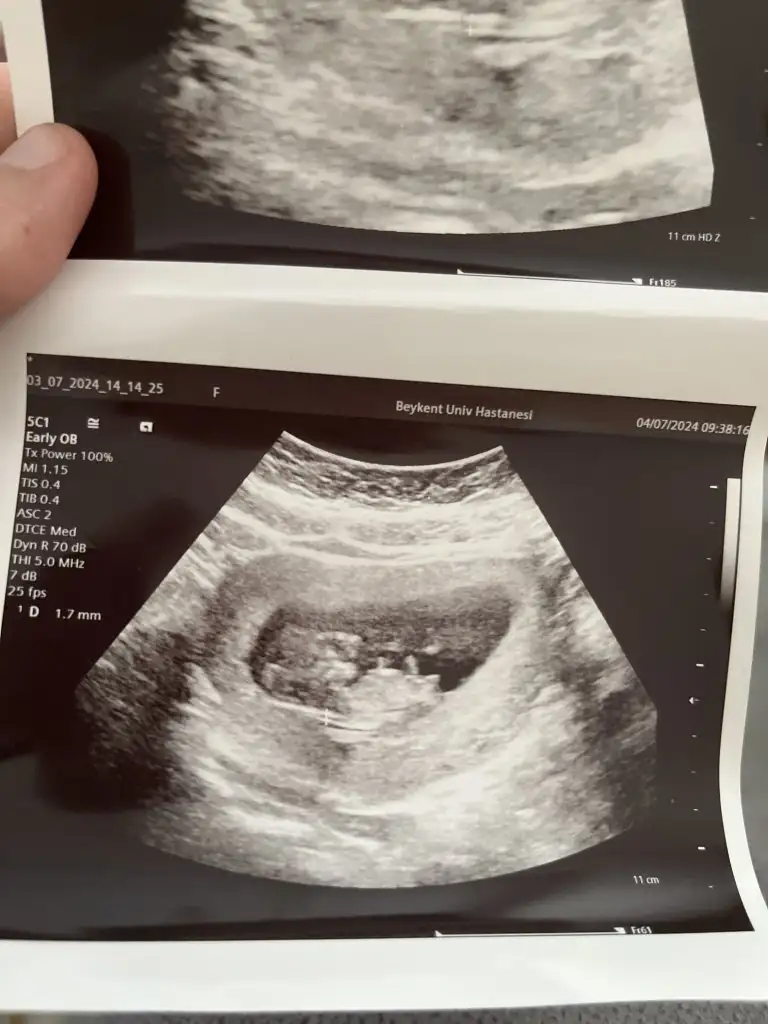

Merhaba arkadaşlar ben de en son 7 haftalıkken doktor kontrolüne gittim kalp atışını duydum herhangi bir risk yoktu bu gün kontrolüm vardı 11+1 olmuşuz uyumlu çıktı burun kemiği normal ense kalınlığı1.7 çıktı gelişim olarak 4.4 küsur cm imiş ben ikili test sordum fetal DNA yapalım ikili 3lü vs gerek kalmaz dedi Panoroma firmasını önerdi en uygun paket 425 dolar ediyor bir üst paket 465 imiş Amerika’ya gidiyormuş 12 gün içinde belli olur dedi cinsiyet de doktora bildiriliyormuş genelde

Teyzeleri tahmininiz var mı cinsiyetle ilgili içime hiç doğmadı tek dileğim sağlıklı olması 37 yaşındayım ilk gebeliğim

Eklentiler

• image.webp

image.webp

34,3 KB · Görüntüleme: 115